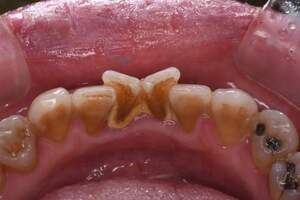

歯石除去

治療前1

治療後1

治療前2

治療後2

| 年齢 | 56歳・男性 |

| 主訴 | 主訴:歯石除去 治療部位:全顎 |

| 治療内容 | 初診検査・歯石除去 |

| 治療期間 | 60分 |

| 費用 | 合計約5,000円 初診検査約3,000〜4,000円 歯石除去約1,000円 (2024年4月現在) (歯の本数や検査内容で料金が変動します。) |

| リスク・副作用 | ・歯と歯の間に隙間ができるので、息が漏れ発音しにくいと感じることがあります。 ・歯ぐきの炎症がある場合は歯石除去中に出血を伴う可能性があります。 ・処置後に歯がしみることがあります。 ・歯ぐきの炎症が軽減すると歯ぐきが引き締まり、歯が長く見えることがあります。 |

| 治療方針 | 歯石除去・ブラッシング指導後SRP(歯ぐきの中に付着する歯石の除去) |

| 特記事項 | ・30年ぶりの歯科医院 ・毎食後の歯ブラシ習慣はあるが1分程度 |

| 担当者所見 | 全体の検査と歯石除去希望で来院されました。 特に下顎前歯部の歯と歯の間の歯石が、笑った時に見えてしまい気になるとのことで、初診検査後に歯石除去を行いました。 ブラッシング指導は歯間ブラシの入れ方と歯ブラシの動かし方をお伝えしました。 今後は治療と共に縁下歯石(歯ぐきの中に付着する歯石)の除去を行なっていく予定です。 |